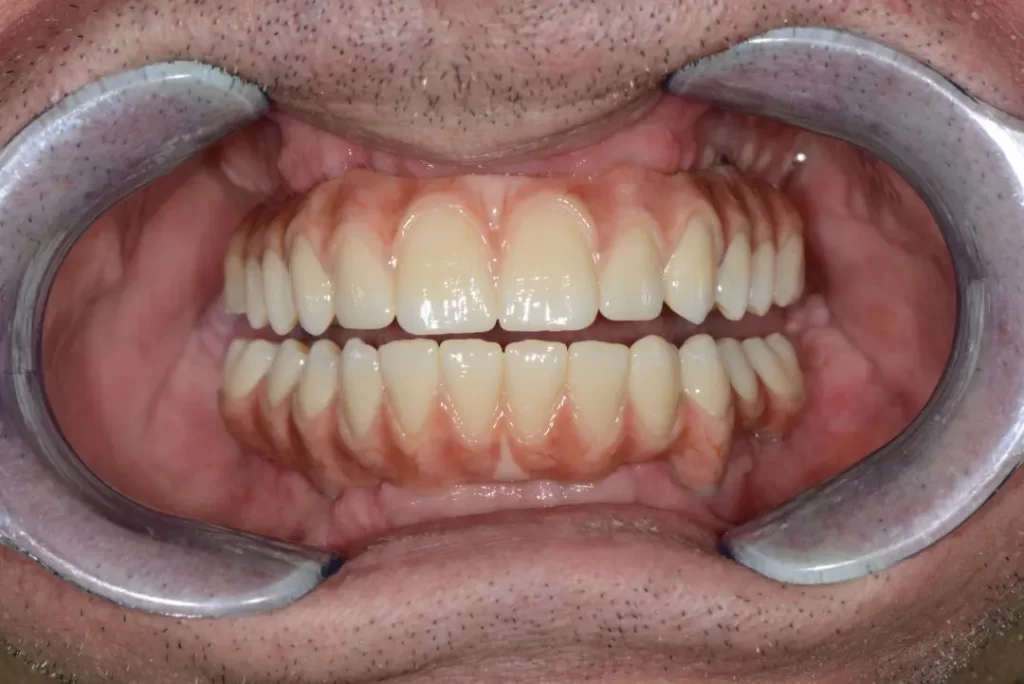

Оригинални зъбни импланти Nobel Speedy за All on 4

През последните години лечението по метода All on 4 създаден от Paulo Malo, придоби широка популярност, поради бързото възстановяване на цялото съзъбие при неизбежната нужда от премахване на всички останали собствени зъби, без използване на методи изискващи по-дълъг период от време за завършване на цялото лечение – синус лифт, костна аугментация и др.

Споделените с Вас моменти, за възстановяване на вашето съзъбие със зъбни импланти по оригиналната методика на Paulo Malo – All on 4 са част от истинската, съвременна дентална медицина, която се практикува в клиниката на Дента Консулт.